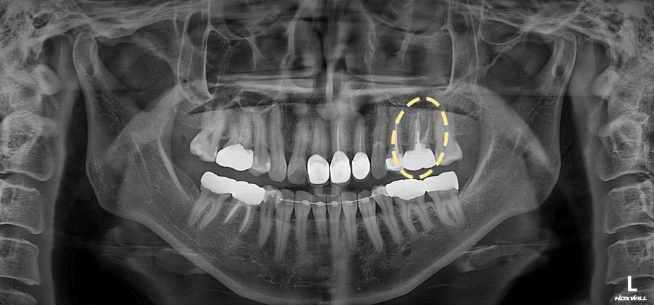

40대 여성 환자분은 2년 전 하악 어금니 치료 후 크라운을 사용 중이셨습니다.

최근 딱딱한 음식을 씹을 때 불편함이 생겨 내원하셨는데요.

일반 엑스레이에서는 특별한 이상이 보이지 않았지만, 3D CT에서는 뿌리 끝에 염증이 확인되었습니다.

미세현미경으로 기존 크라운 내부를 들여다보니 충전이 완전하지 않은 근관이 있었고, 그 틈으로 세균이 다시 들어간 흔적이 보였습니다.

정밀 장비와 경험이 없다면 놓치기 쉬운 부분이죠.